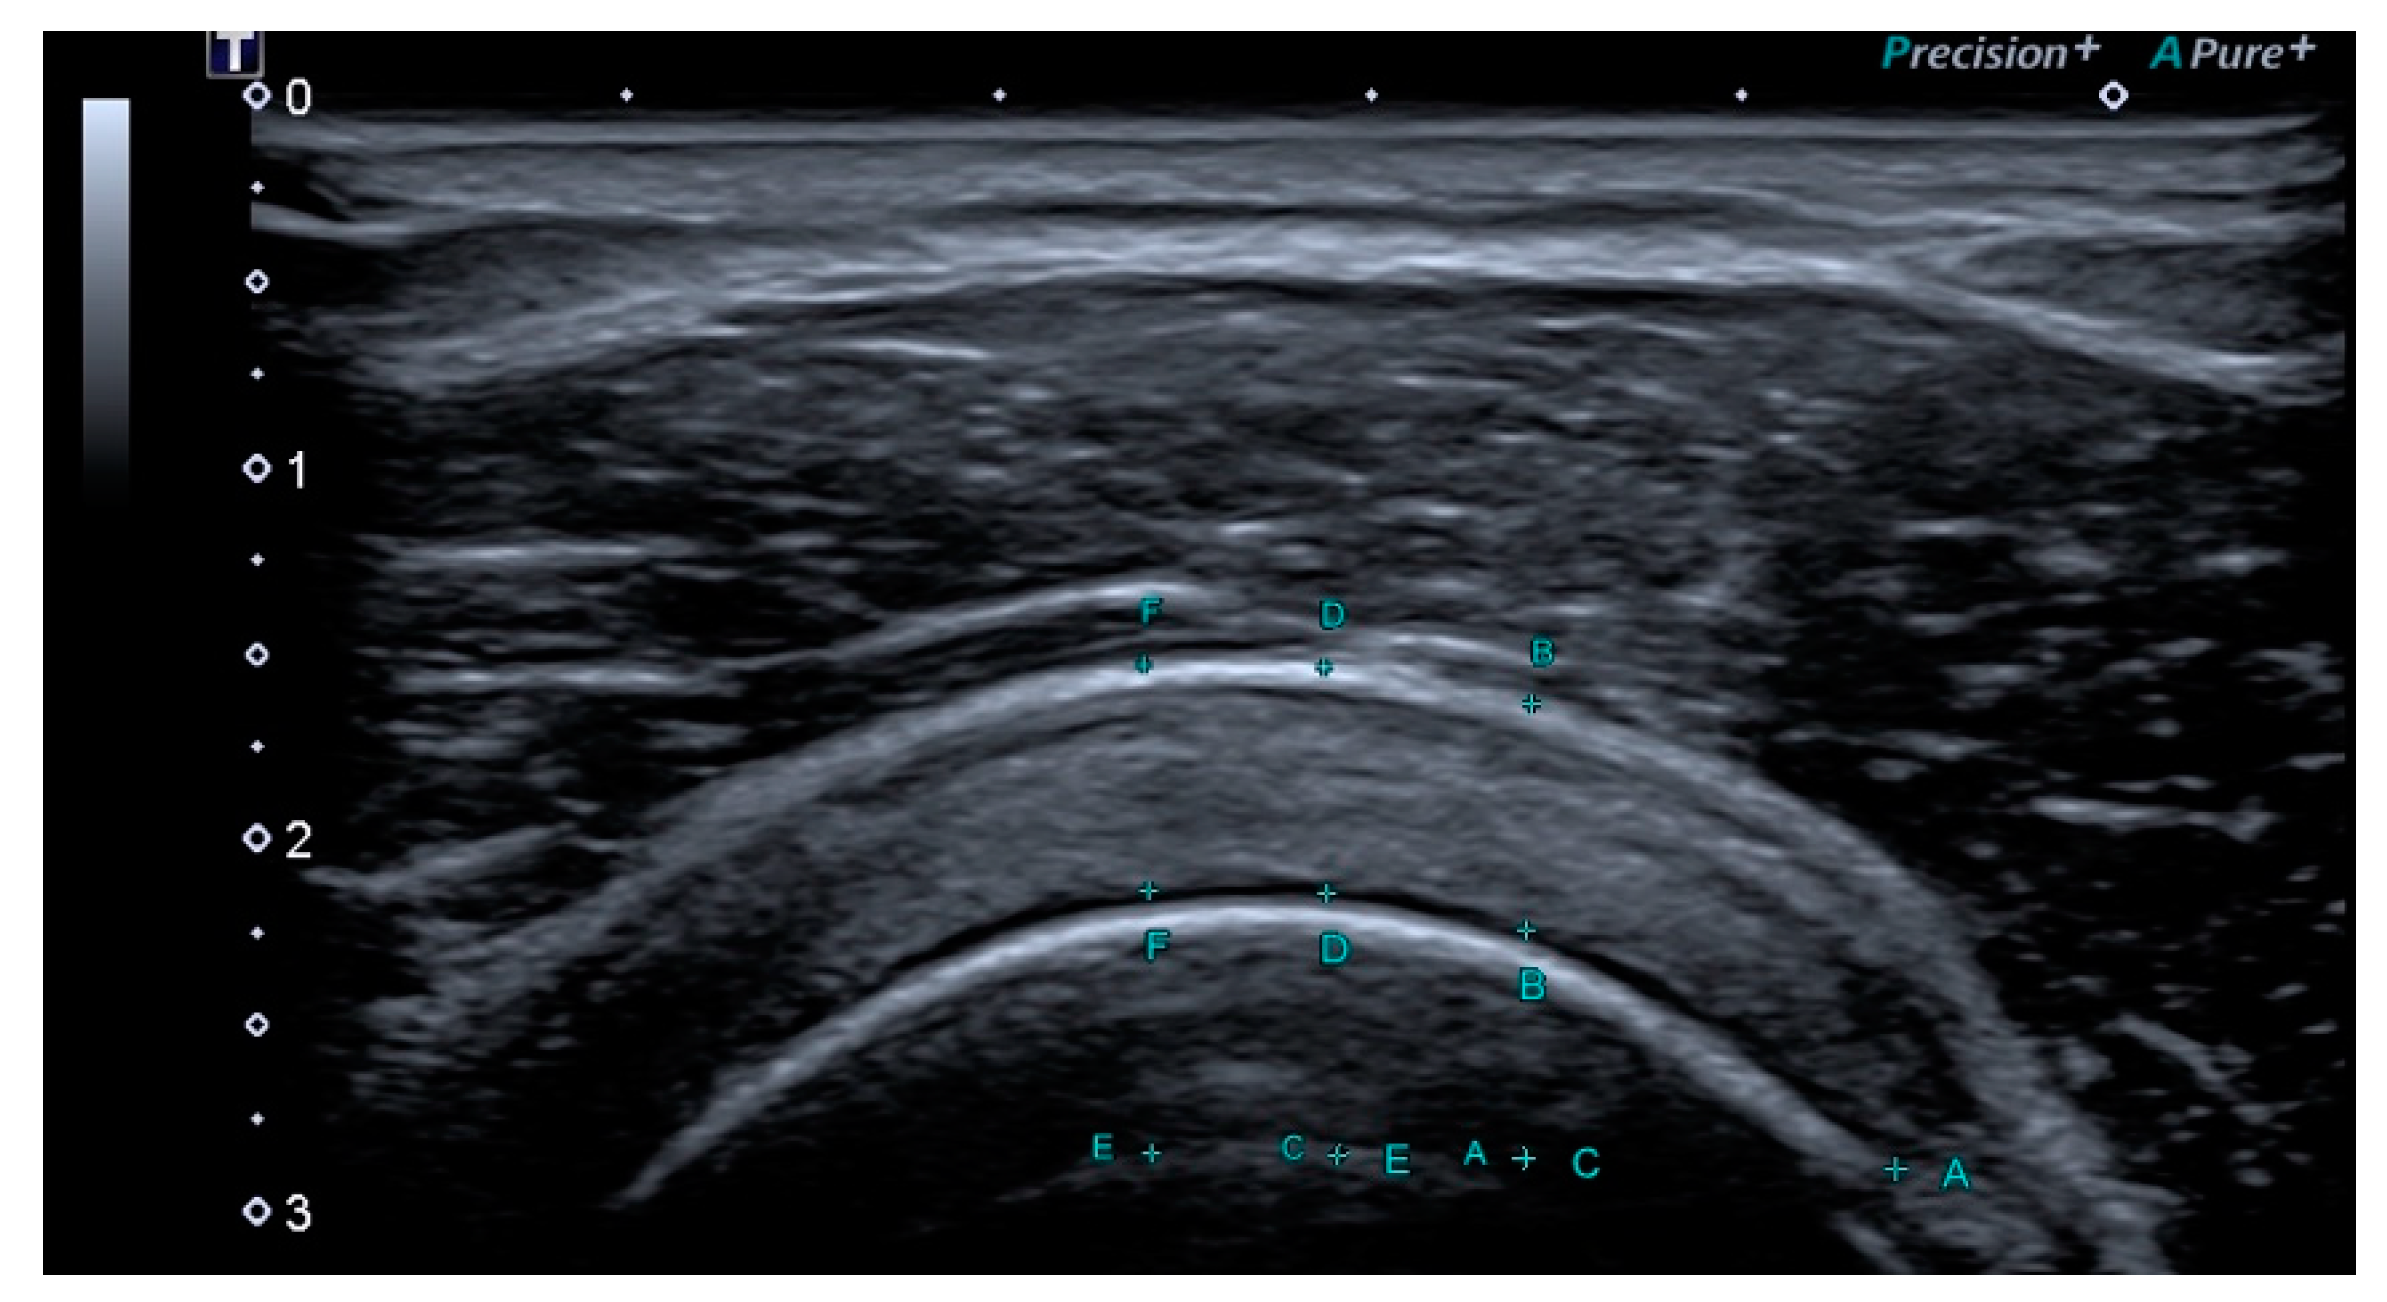

2.2.1. Outcomes Ultrasound Evaluation

2.2.2. Ultrasound Evaluation